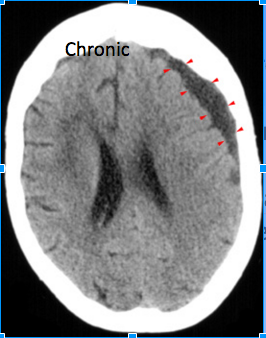

Chronic Subdural hematoma: Whats importnat to notice in this CT?

Crescent shaped chronic subdural hematoma (arrowheads)

Notice

the low attenuation due to reabsorbtion of the hemorrhage over time.